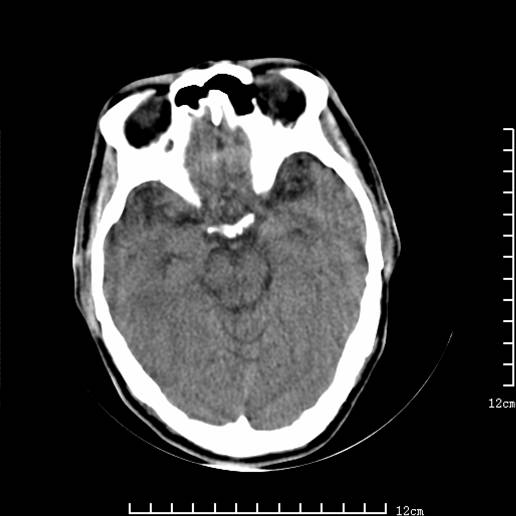

以下图像分别是3月25日凌晨及下午图像、3月27日、4月16日的ct图像。

3月25日下午

1)左侧额颞顶叶、岛叶及基底节区(相当于左侧大脑中动脉供血区)大面积脑梗塞。2)右侧基底节区腔隙性脑梗塞。